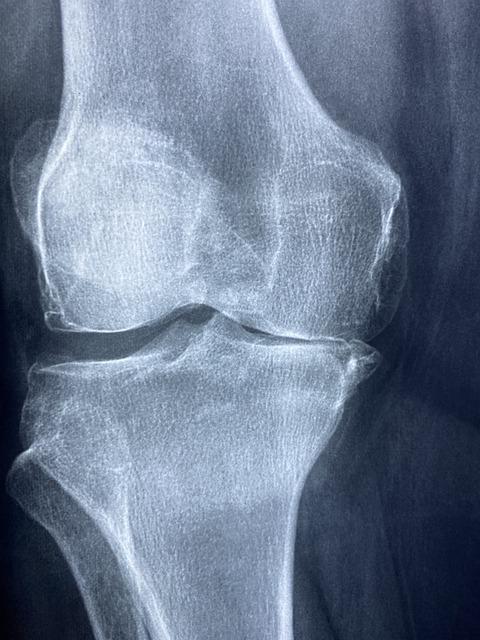

시서스 효능 - 뼈 건강

고대시대부터 사용된 시서스는 부려진 뼈를 잘 붙고 차오르게 하고 시서스 효능 붓기와 염증을 내려주어

골절의 빠른 회복을 도와 골다공증과 같은 질환을 예방하는 데 효과가 있으며 뼈 손실을 줄이고 비만으로 인한 약해진 관절 회복에 도움을 줍니다.